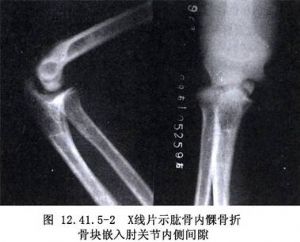

肱骨内髁骨折切开复位术用于肱骨内髁骨折的治疗。肱骨内髁骨折罕见,占儿童肘部骨折1%以下。多见于8~14岁儿童(图12.41.5-1~12.41.5-3)。